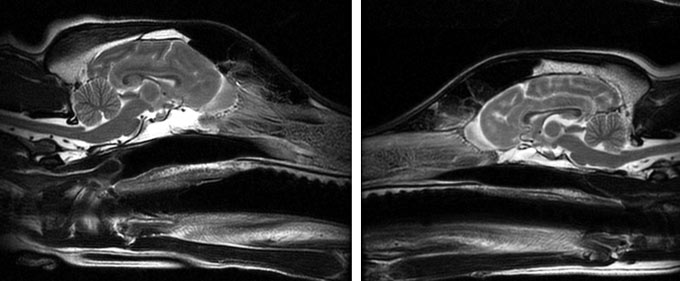

Certain brain regions take on a different shape in a basset hound’s brain (left) than the brain of a border collie (right).

Marc Kent & Erin Hecht